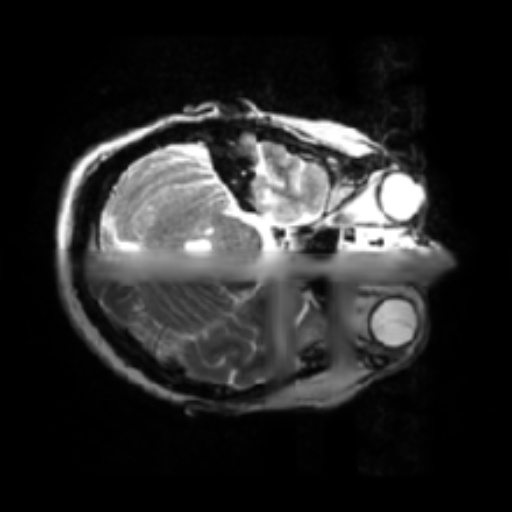

- 1.2 Examples of homogeneity in medical imaging modalities illustrating the similarity of the underlying subject (PET, CT, and MRI).

- (b) CT scan of the brain99footnotemark: 9

- (c) MRI of the brain1111footnotemark: 11

Thirdly, while seeming counter to the second point, while in a broad sense medical images are heterogeneous due to the very different imaging techniques and separation based on medical specializations (head scans vs foot scans), within a given data type, there is very high visual similarity. For example, all chest X-rays will look very similar due to standardized acquisition methods and tools, but also in large part, due to the high homogeneity of the human biology, see figure 1.2. For the chest scan example, most human bones and organs will have almost identical structures, similar sizes, and composition. Furthermore, the way these scans are collected is standardized, so the patients will all be positioned at the same angle and distance from the imaging machines. This is true even for data samples that have completely different labels, as the characteristics that indicate one diagnosis or another are often identified by very small, granular differences, which are visually very small in absolute terms. This poses a challenge to researchers in the sense that they can’t directly adapt many of the more recent and best-performing classes of Self-Supervised methods, such as contrastive learning. This has allowed us to develop methods that are tailored specifically for medical images.